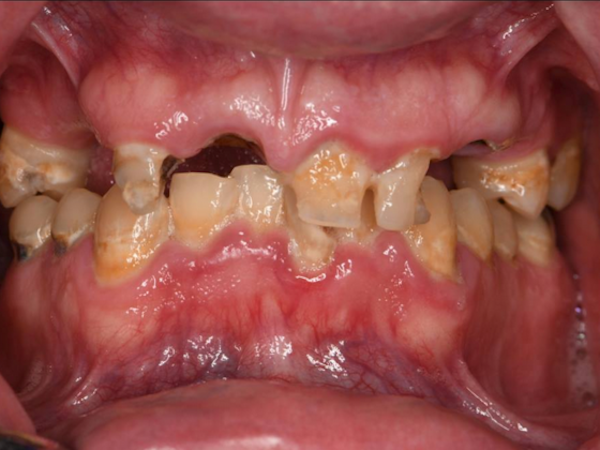

See the Difference

We Can Make

Our friendly team provides healthy smiles to patients who have endured dental trauma and oral health issues.

Dr. Jovanovski has been in practice since 2009. Since then, he has been providing patients with healthy, functional smiles, no matter how long they have forgone dental treatment. Our dentistry practice is known for taking on difficult cases and returning healthy smiles to patients who have endured dental trauma and extensive oral health issues.